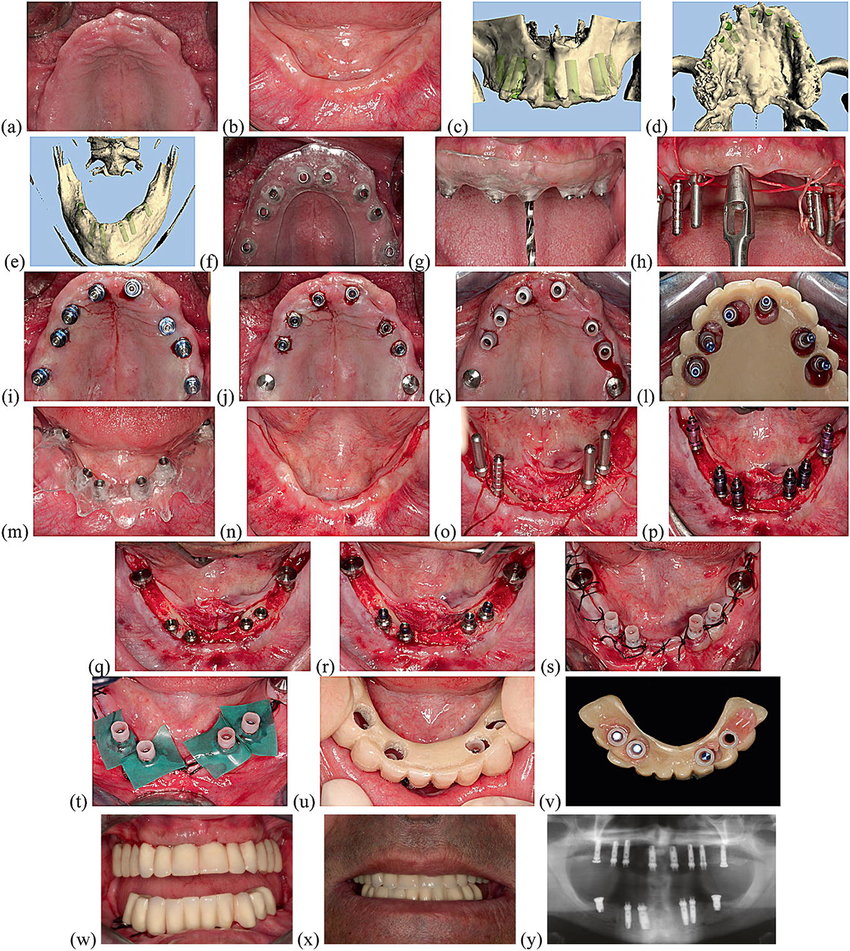

Trong thực tế lâm sàng, quy trình phục hình tức thì là gì thường được giải thích gắn liền với từng bước cụ thể. Đầu tiên, bệnh nhân được thăm khám, chụp CT Cone Beam và lập kế hoạch cấy 6 trụ Implant phù hợp với cấu trúc xương hàm.

Ca phẫu thuật All on 6 được tiến hành trong 1–2 giờ (hoặc hơn tùy trường hợp), trong điều kiện vô trùng, với gây tê tại chỗ hoặc tiền mê tùy nhu cầu và chỉ định. Ngay sau khi đặt trụ, bác sĩ kiểm tra lại độ ổn định sơ khởi từng trụ để quyết định có thể tiến hành Immediate Loading hay không.

Nếu điều kiện cho phép, bác sĩ sẽ tiến hành lấy dấu hàm bằng vật liệu lấy dấu chuyên dụng (như silicon, cao su) hoặc sử dụng máy scan trong miệng 3D, rồi gửi dữ liệu sang labo. Tại đây, kỹ thuật viên sẽ chế tác hàm răng tạm – thường là hàm nhựa acrylic hoặc composite gia cường – theo thiết kế đã được thống nhất với bác sĩ về khớp cắn, hình thể và thẩm mỹ.

Thông thường trong vòng 24 giờ, hoặc tối đa 48–72 giờ, hàm tạm sẽ hoàn thiện và được đưa lại cho bác sĩ. Ở lần hẹn kế tiếp, bác sĩ sẽ gắn cố định răng tạm trên Implant bằng hệ thống vít, bệnh nhân không thể tự tháo ra. Từ đây, giai đoạn tải lực tức thì bắt đầu, với chế độ ăn nhai được kiểm soát và lịch tái khám định kỳ để theo dõi quá trình tích hợp xương.